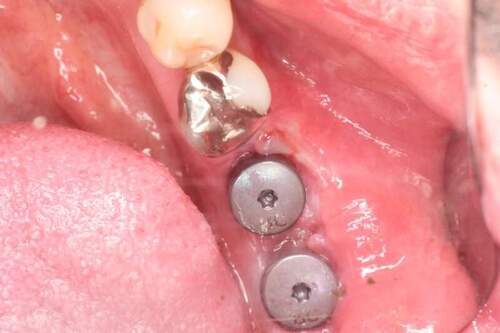

口腔内写真

- Befor

- After

| 年齢 | 50代・男性 |

|---|---|

| 主訴 | 部位:左下6番7番 主訴:左下奥歯腫れて痛い。 |

| 治療内容 | 左下6番抜歯、左下6番7番骨造成、インプラント埋入 |

| 治療費 | 合計:1,232,000円 ・内訳 診断料:55,000円 サージカルガイド2本:66,000円 GBR:110,000円×2本 埋入料:165,000円×2本 静脈内鎮静麻酔:77,000円 2次OPE:22,000円×2本 仮歯:55,000円×2本 上部構造(フルジルコニア):165,000円×2本 (2023年1月現在) |

| 治療期間 | 約8ヶ月 |

| リスク・副作用 | リスク・副作用 |

| 治療方針 | 元々支台歯に負荷がかかりやすいとされている延長ブリッジを抜歯し、1本単体でしっかりかめるようにインプラントを2本埋入した。骨吸収も進んでいたため、※GBR法で骨造成を同時に行った。 治療と並行して、全顎的な歯周病治療も行い、今後は歯周病が進行しないよう、こまめにメンテナンスに通っていただく。 |

| 特記事項 | ※1 GBR・・・骨再生誘導法。骨の高さや厚みを人工骨や人工膜などを使用し再生する方法 |

| 担当者所見 | 6番は歯根分割された被せ物が7番の欠損部との延長ブリッジとされており、強い咬合と歯周病も相まって負荷がかかり動揺し、歯として機能しなくなったため、抜歯となった。 |